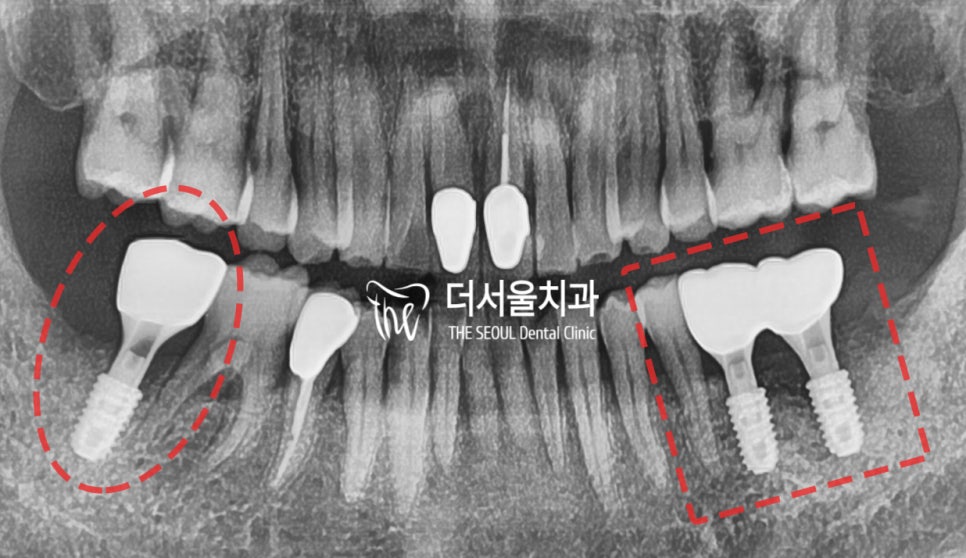

엑스레이를 보면 아래 양 쪽으로 문제가 있죠.

이렇게 2개의 증세를 볼 수 있는데

사진에서 보실 수 있는 것 처럼,

사랑니 당일 발치 후에 임플란트 3개를 심었고

4개월 경과에 따라서 뼈가 잘 아물어서

지르코니아 크라운까지 올려드린 것을

보실 수 있습니다.